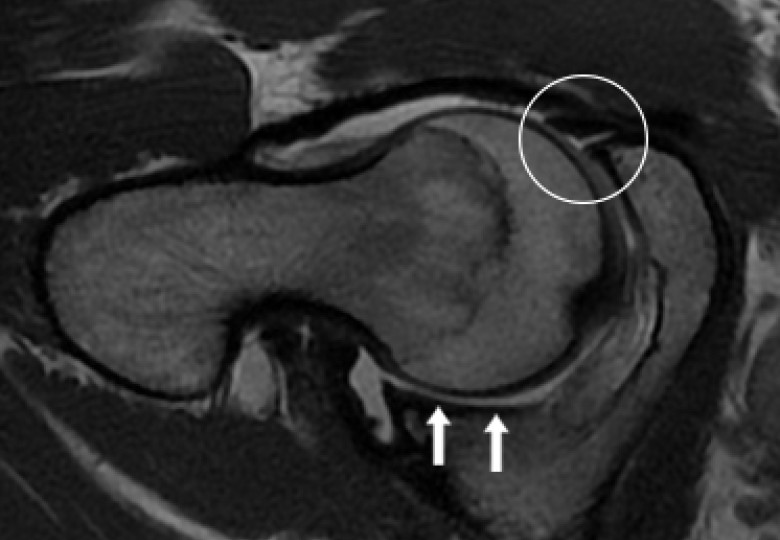

• Labral hyperplasia ( enlargement of the cartilage at the margin of the hip socket) was a predictor of microinstability.